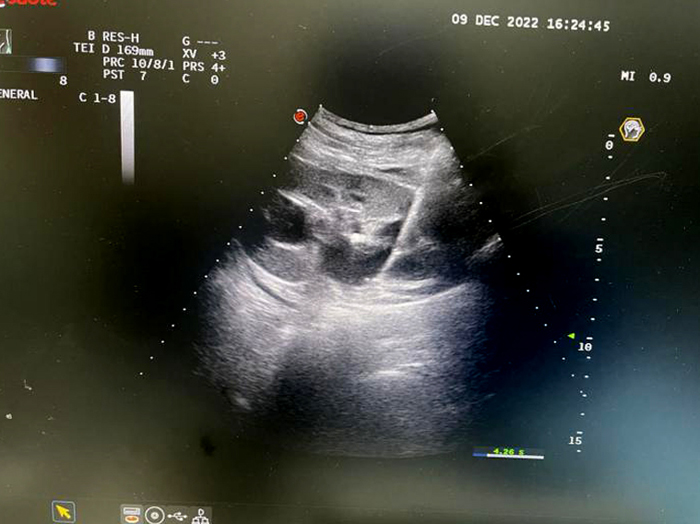

超聲引導下腫瘤消融治療是在實時超聲的監視引導下,應用專門的治療針,達到不開刀對體內的腫瘤原位滅活的一門新技術手術切除相媲美,技術成熟,損傷輕微,費用低廉,延長患者生命,提高生活質量。這種治療方式,適用于各類型肝癌,尤其是不能手術,或術后復發、轉移性腫瘤,以及甲狀腺腫瘤、子宮肌瘤等實體瘤的治療。

肝臟腫物微波消融術

子宮多發肌瘤微波消融術